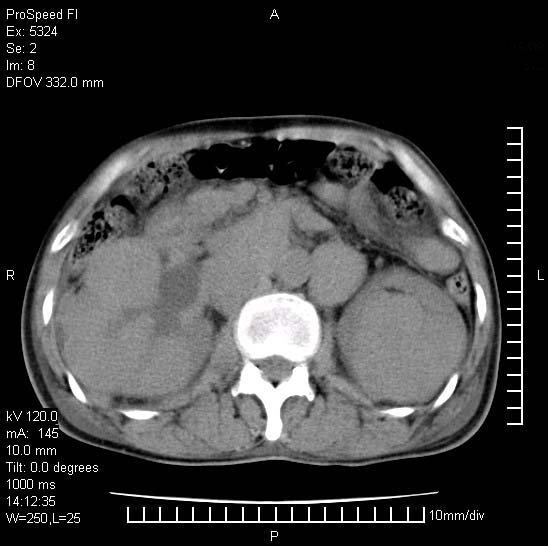

患者阴囊肿大14月,腰痛2个月,咳嗽,咳痰1周,患者现在肾功异常,做增强有些担心,我们用的是欧乃派克.

右侧肾癌伴腹膜后淋巴结转移!

右侧肾癌后腹膜转移,腹腔少量积液

腹膜后淋巴结肿大包饶腔静脉,双肾病变,建议增强

双肾均有软组织密度舯物,腹膜后淋巴结肿大包饶腔静脉------考虑为恶性占位病变,转移瘤可能。

支持:双肾均见软组织密度肿块影,腹膜后淋巴结肿大包绕腔静脉------考虑为恶性占位病变,转移瘤可能。

1)考虑双肾恶性肿瘤(肾癌?)。2)腹膜后淋巴结肿大,多为肿瘤转移所致。

腹腔积液,双肾均有稍高密度肿块,主动脉旁广泛淋巴结肿大,融合,无显著肿块坏死征像,多考虑淋巴瘤累及双肾,不排除肾癌伴转移(肾癌这么大应该较多坏死了),另阴囊肿大,不知是实质肿大还是阴囊积液,如是是积液,多为腹腔肿块压近睾丸静脉所致,如是是实性的,多为淋巴瘤

1、淋巴瘤,双肾转移瘤;2、双侧肾癌,伴有腹膜后淋巴结转移。

双肾均有软组织肿块伴腹膜后淋巴结肿大融合,右侧结肠旁沟积液;考虑恶性肿瘤。转移瘤?淋巴瘤?

双肾增大,腹膜后多发肿大淋巴结影.首先考虑淋巴瘤.

双肾增大,结合腹膜后淋巴结肿大,考虑双肾恶性肿瘤并转移可能。

双肾癌并腹膜后淋巴结转移

考虑恶性淋巴瘤侵及双肾,腹膜后淋巴结肿大。